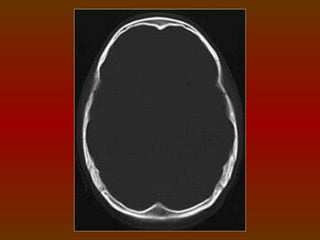

TC CRÂNIO AXIAL

COM JANELA ÓSSEA

TC CRÂNIO AXIAL COMJANELA ÓSSEA